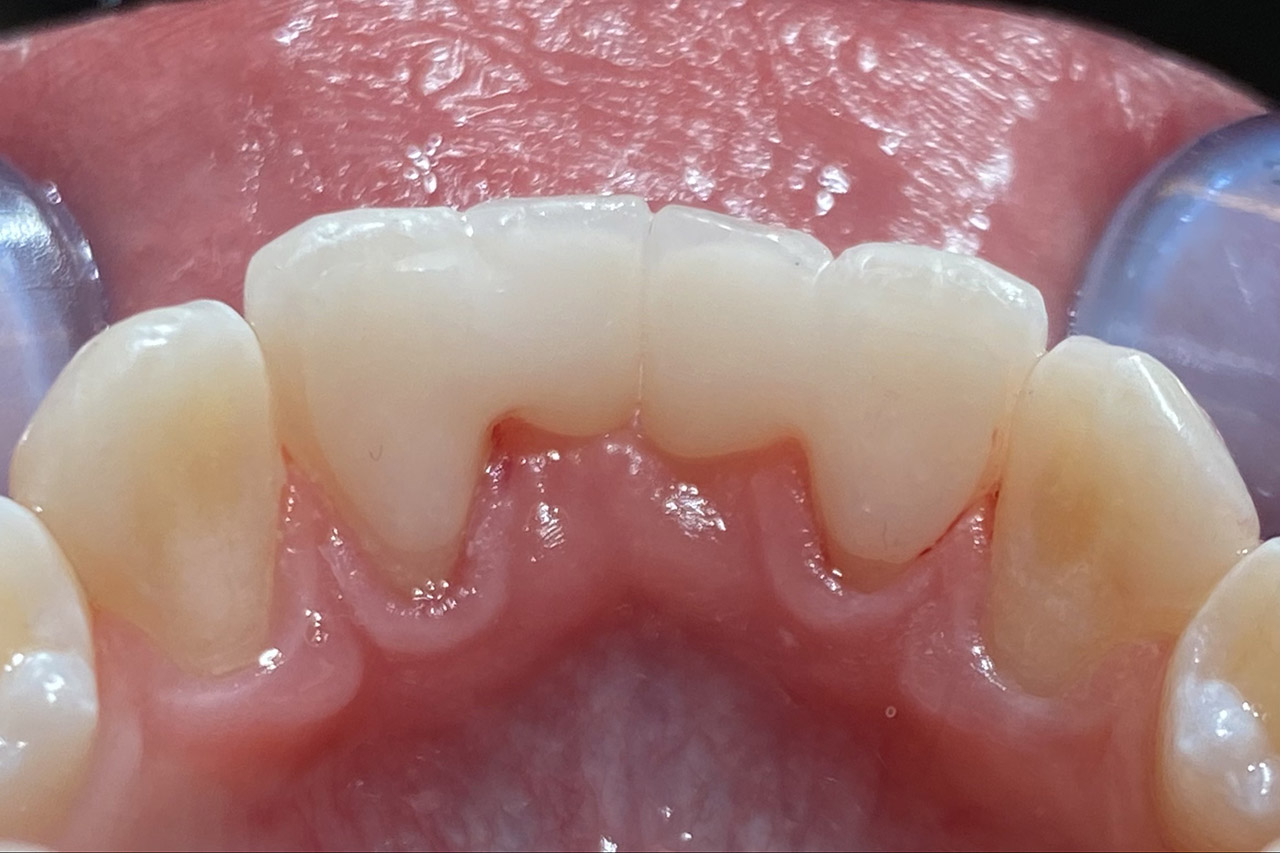

Traumatologie und Endodontie:

Nach Unfall/Sturz mittlerer Schneidezahn auf Gingivaniveau abgebrochen, Pulpa weit eröffnet, beide Nachbarzähne ebenfalls frakturiert.

Erstversorgung: Pulpektomie der Kronenpulpa, MTA, provisorischer Verschluß mit rosa Glasionomerfüllung.

Wiederaufbau der Nachbarzähne mit mitgebrachten (plus 1 Stein) Zahnstücken mit Kunststoff ergänzt und adhäsiv verklebt.

2. Schritt nach Aushärtung von MTA: Entfernung der Kronenpulpa im Bruchstück zur Vermeidung von Verfärbung, Füllung mit Kunststoff.

Adhäsives zementieren des abgebrochenen Zahnstücks.